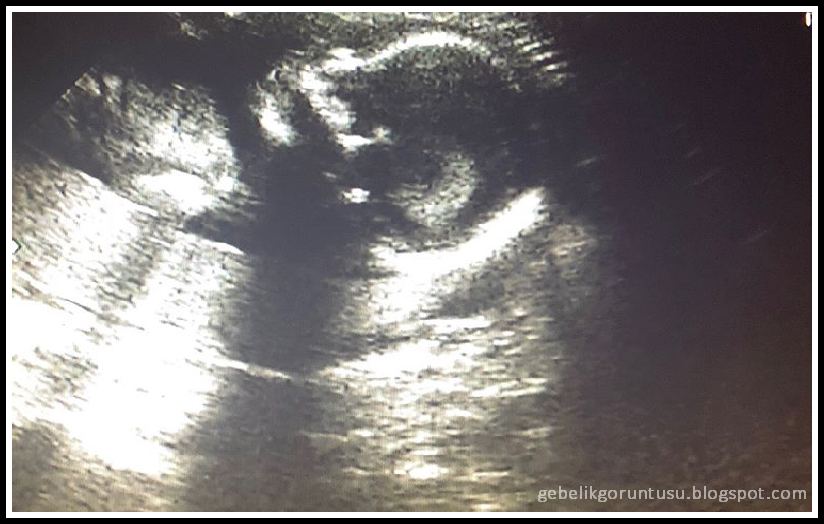

18 Haftalık Gebelik (Hamilelik) Ultrason Görüntüleri

18 Haftalık Gebelik (Hamilelik)

18 haftalık gebelik ultrason görüntüleri